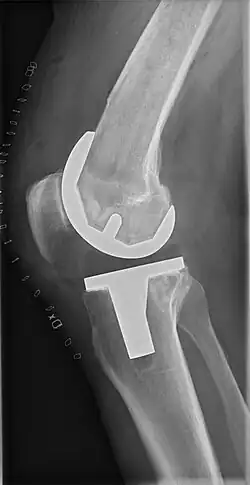

Knee replacement, also known as knee arthroplasty, is a surgical procedure to replace the weight-bearing surfaces of the knee joint to relieve pain and disability, most commonly offered when joint pain is not diminished by conservative sources.[1][2] It may also be performed for other knee diseases, such as rheumatoid arthritis. In patients with severe deformity from advanced rheumatoid arthritis, trauma, or long-standing osteoarthritis, the surgery may be more complicated and carry higher risk. Osteoporosis does not typically cause knee pain, deformity, or inflammation, and is not a reason to perform knee replacement.

Knee replacement surgery can be performed as a partial or a total knee replacement.[3] In general, the surgery consists of replacing the diseased or damaged joint surfaces of the knee with metal and plastic components shaped to allow continued motion of the knee.

The surgery involves exposure of the front of the knee, with detachment of part of the quadriceps muscle (vastus medialis) from the patella. The patella is displaced to one side of the joint, allowing exposure of the distal end of the femur and the proximal end of the tibia. The ends of these bones then are cut accurately to shape, using cutting guides oriented to the long axis of the bones. The cartilages and the anterior cruciate ligament are removed; the posterior cruciate ligament also may be removed but the tibial and fibular collateral ligaments are preserved.[20] Whether the posterior cruciate ligament is removed or preserved depends on the type of implant used, although there appears to be no clear difference in knee function or range of motion favoring either approach.[20] Metal components are then impacted onto the bone or fixed using polymethylmethacrylate (PMMA) cement. Alternative techniques exist that affix the implant without cement. These cement-less techniques may involve osseointegration, including porous metal prostheses. Finally, stability and range of motion are checked, followed by irrigation, hemostasis, placement of hemovacs, and closure.[21]

Femoral replacement

A round-ended implant is used for the femur, mimicking the natural shape of the joint. On the tibia the component is flat, although it sometimes has a stem that goes down inside the bone for further stability. A flattened or slightly dished high-density polyethylene surface is then inserted onto the tibial component so the weight is transferred metal to plastic, not metal to metal. During the operation any deformities must be corrected, and the ligaments balanced so the knee has a good range of movement, and is stable and aligned. In some cases the articular surface of the patella also is removed and replaced by a polyethylene button cemented to the posterior surface of the patella. In other cases, the patella is replaced unaltered.